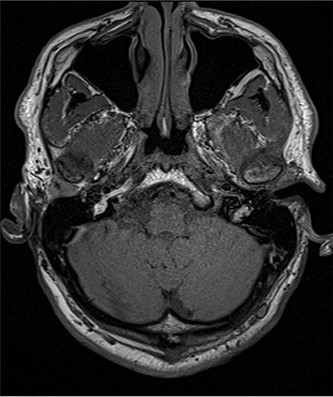

A 56- year old male was presented in the Outpatient Department of Otolaryngology Clinic with main complaint of complete aural atresia of the right ear. The clinical examination revealed that there was no external auditory canal in the right ear (Fig. 1) and hearing loss was altered (Fig. 2). There was no symptomatology in the left ear and the anatomic structures were completely normal. Blood test was normal, and there were no other medical issues from the personal history. The computed tomography (CT) scan and mainly the magnetic resonance imaging (MRI) of the temporal bone revealed no mastoid air cells and no external auditory canal and auricle (Figs 3 and 4). There was a normal anatomy of the internal auditory canal on both sides. Left side of the external auditory canal was normal. Diagnosis of this anatomical malformation was compatible with congenital atresia of the external auditory canal on the right temporal region. The patient decided to proceed to surgery many years after the first diagnosis. Some weeks ago, canalplasty and tympanoplasty were performed by our surgery team. During surgery, a graft has been obtained in order to formate the covering of the new canal. The incision was made behind the ear at the level of temporal bone, and the graft needed is removed from the temporal fascia and inserted as covering of the new canal. The aim is to create a new anatomic pathway resembling a normal external acoustic canal by drilling the atretic bone and removing the present tissue (Figs 5 and 6).

Preoperative examination includes blood tests, audiogram and mostly imagistic examination. CT scan and MRI are necessary for evaluating the surrounding anatomical structures, the deformities and are quite helpful in the surgery plan. In this present case, the imagistic examination revealed unilateral mastoiditis, right atresia of the external acoustic canal and normal anatomy of the other unaffected side. According to Jahrsdoerfer grading system [4], the surgical success can be based on some clinical features regarding the profile of candidates for operation. Based on CT scan and identifying the anatomical structure, such as oval window open, middle ear space, facial nerve, malleus incus complex, mastoid pneumatization, incus-stapes connection, round window and external ear, a score is calculated, and if it is >7/10, surgical success is predicted [5, 6]. The treatment of this anatomical malformation is only surgical repair, resulting in the formation of a new bony canal resembling the external auditory one, by drilling the atretic bone and widening the closed space by removing the stenotic tissue [7]. Repair of the stenotic canal can be succeeded by anterior or posterior approach. In our case, anterior approach has been chosen. The mastoid antrum approach as and operative technique is quite reliable [8]. Removal of the stenotic and fibrotic abnormal tissue requires drilling of the atretic plate over the temporal line behind the glenoid fossa. The drilling stops at the borders of the anterior epitympanium. When the new canal is formatted, it is covered by graft. The goal is to maintain the width of new aural canal. The reconstructed auricle requires use of porous polyethylene material (MedPor) or autologous rib cartilage [8, 9]. In our patient, the auricle was repaired some years ago before the surgical repair of the atretic external auditory canal.